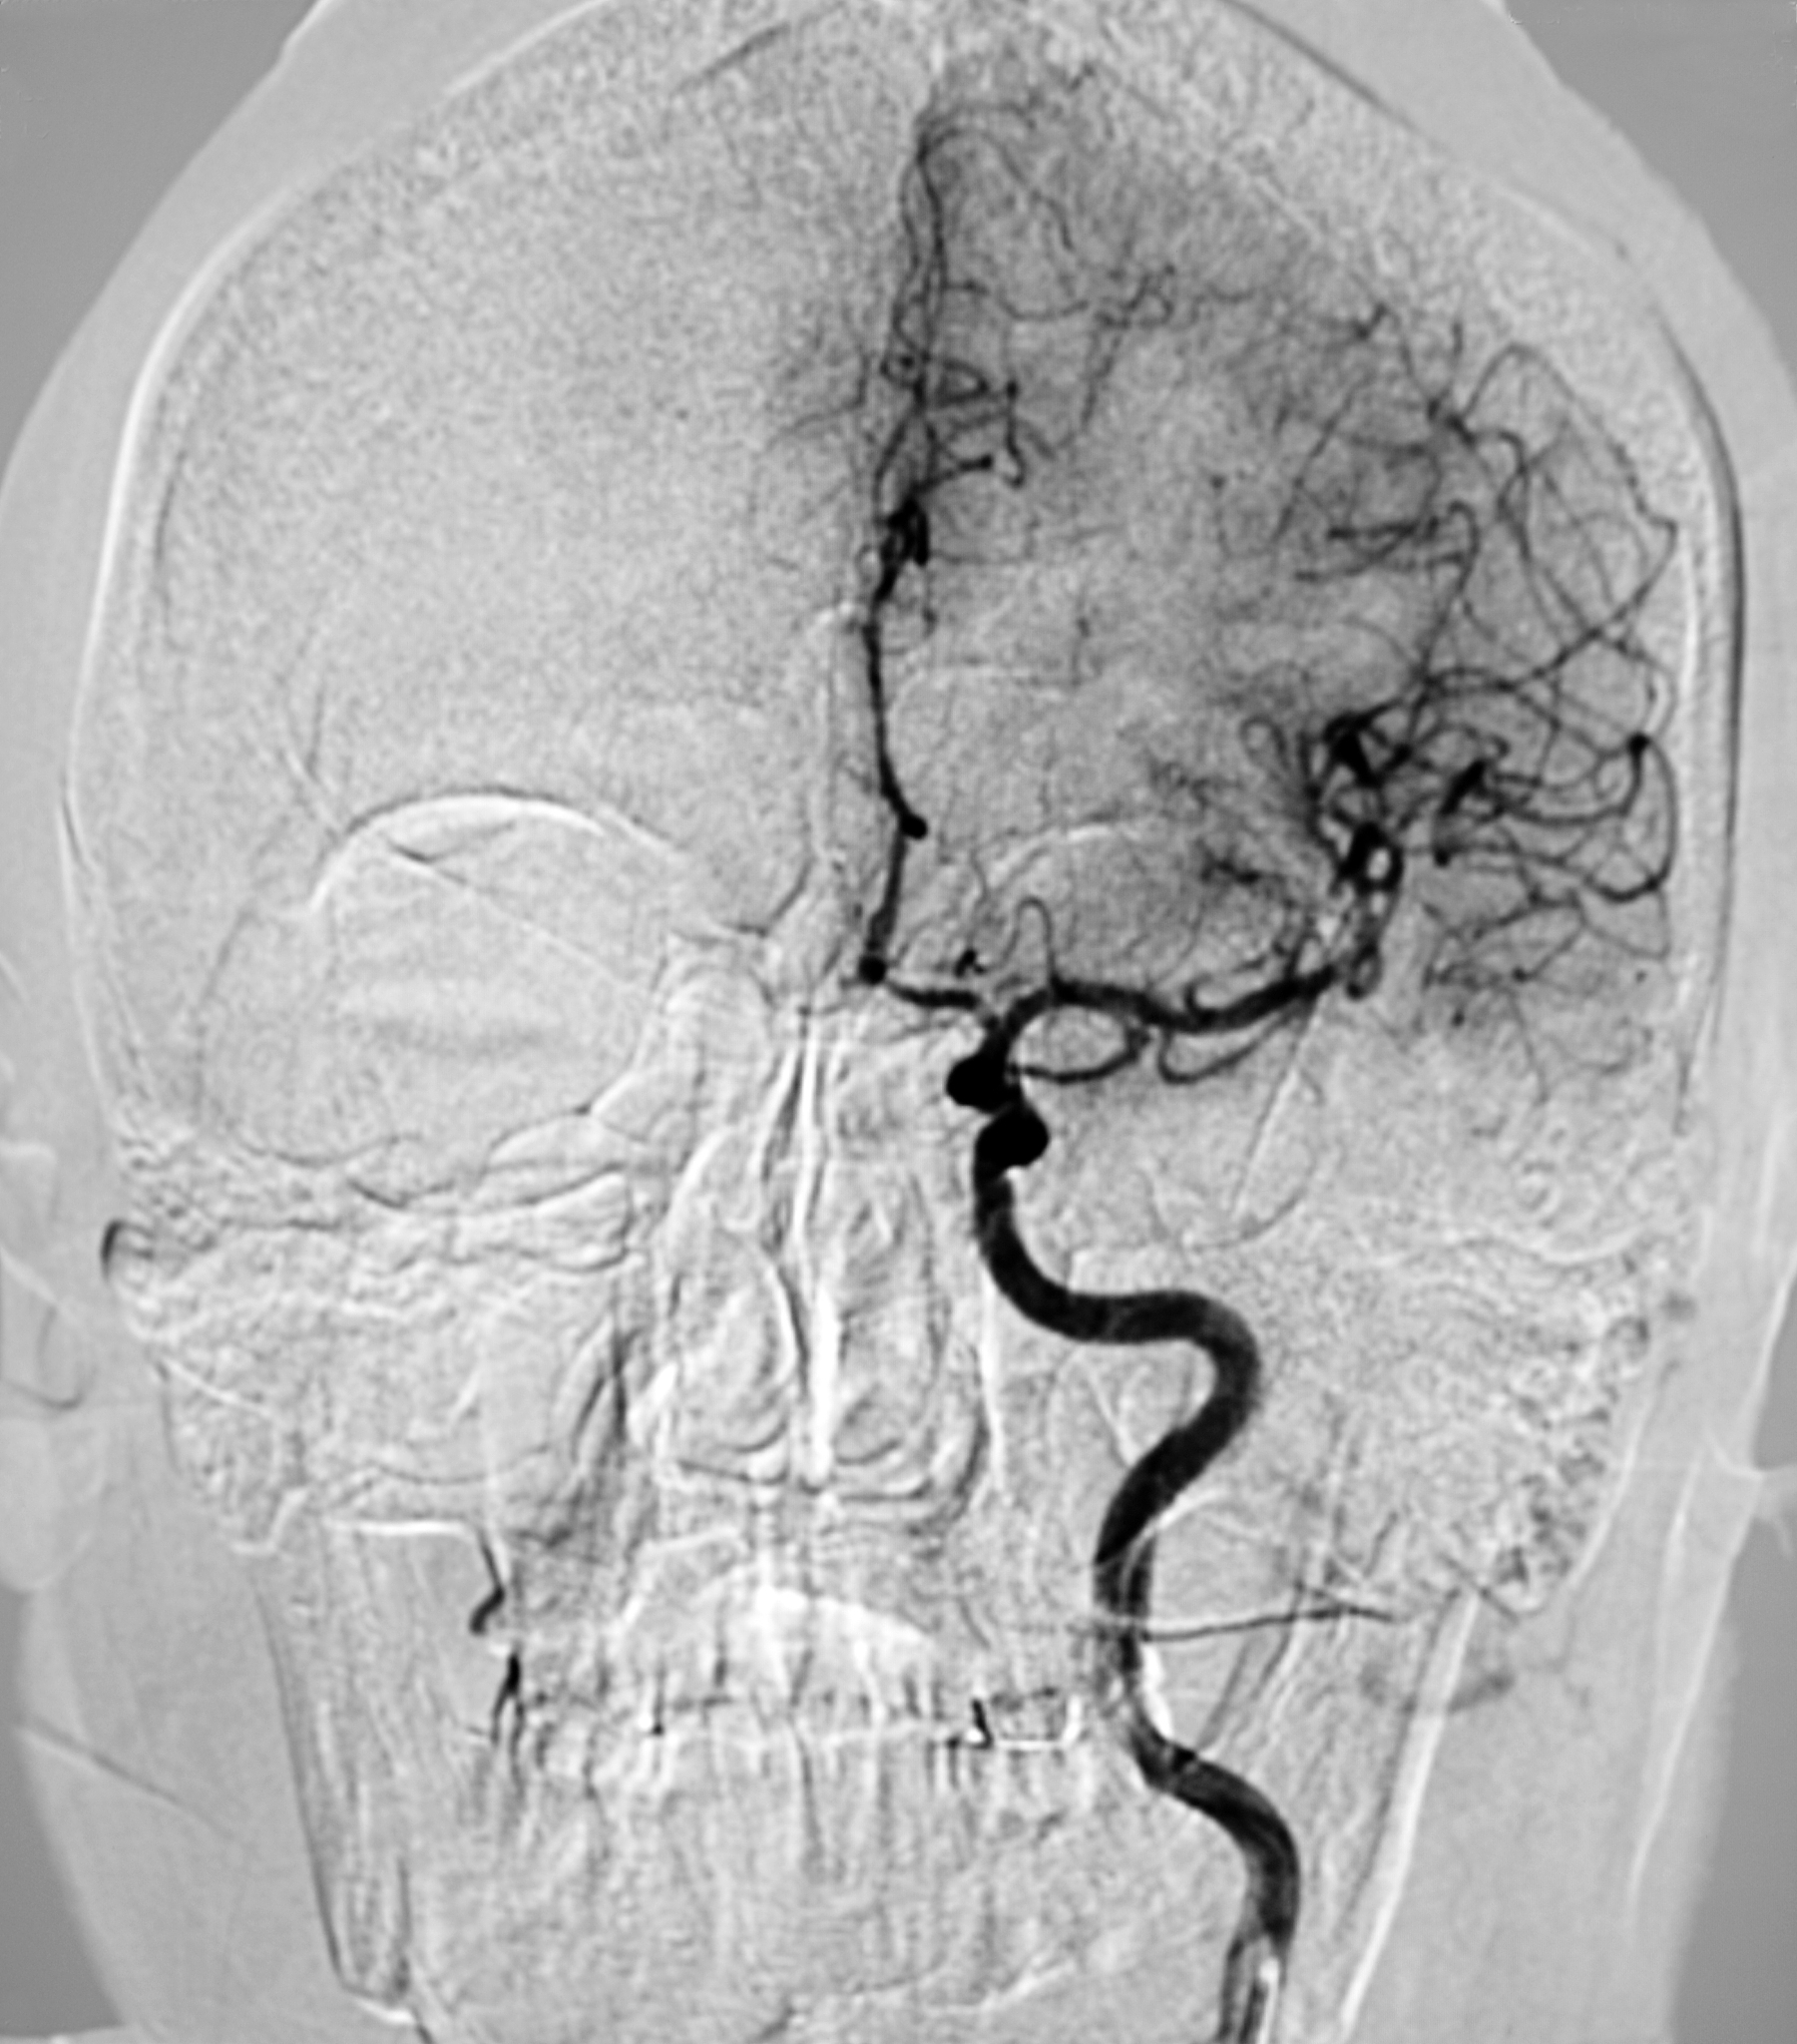

超声造影检查诊断为右侧颈动脉易损性斑块破裂形成溃疡,且合并漂浮血栓形成,右侧颈内动脉起始部中度狭窄。

右侧颈动脉易损性斑块破裂及血栓形成 - 超声造影检查结果